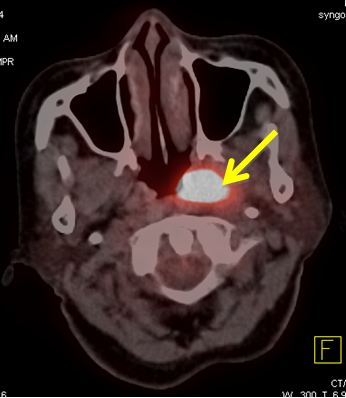

Trên lâm sàng và CT không phát hiện được hạch cổ. Nên kế hoạch điều trị là: xạ trị đơn thuần, với tổng liều vào u vòm là 70 Gy, vào vùng cổ 2 bên 50 Gy.

Trên PET/CT phát hiện hạch di căn vùng cổ trái, nên đã thay đổi giai đoạn bệnh, và làm thay đổi kế hoạch điều trị: xạ trị kết hợp hóa chất, tổng liều vào u vòm: 70Gy, liều vào hạch vùng cổ trái: 70Gy, dự phòng vùng cổ phải: 50Gy.

Hình 2: Hình ảnh PET/CT phát hiện thêm được hạch cổ phải, CT bỏ sót không thấy

Do PET/CT có độ nhạy và độ đặc hiệu cao hơn nhiều so với CT (khoảng 30% hạch cổ di căn mà lâm sàng và CT bỏ sót), nên đã làm thay đổi giai đoạn bệnh và từ đó làm thay đổi thái độ điều trị cho người bệnh.